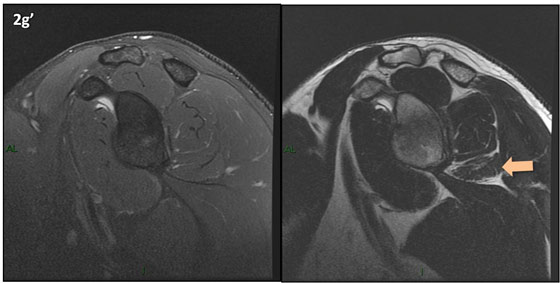

Figura 2 (a-j)': Imagens consecutivas de RM no plano sagital nas ponderaçõesT2 com supressão de gordura (DP SG) à esquerda e T2 à direita. Clique na seta para passar as imagens.

Figuras 2b a 2j’: Acompanhando o tendão do redondo menor (seta amarela fina) é possível notar lipossubstituição ao redor da junção miotendínea (setas amarelas grossas) e a atrofia principalmente da porção mais lateral (seta salmão). A porção mais medial (seta branca) tem volume preservado.

Repare que estas alterações também não são evidentes nas imagens com supressão de gordura no plano sagital.

Chafik et al. também relataram a presença de um pequeno nervo motor acessório em número variável que se insere na porção lateral do músculo redondo menor. O nervo acessório, ao contrário do principal, tem um curso reto e extra-fascial, sendo menos vulnerável aos efeitos compressivos. De fato, nos casos da atrofia parcial do redondo menor, é mais frequente a atrofia da porção mediodorsal com preservação da porção lateroventral, o que poderia ser explicada pela presença do ramo acessório mais lateral do nervo axilar, embora atrofia isolada do componente lateroventral tenha sido reportada em cerca de 17% dos casos de atrofia de apenas uma porção, o que pode ter sido causada por lesão do nervo acessório. No caso do paciente deste mês, a atrofia é mais evidente nesta porção mais lateral e ventral do redondo menor.

É importante que o protocolo de ressonância magnética do ombro tenha sequências ponderadas em T1, T2 ou densidade protônica (DP) sem supressão de gordura em pelo menos dois planos, idealmente nos planos coronal e sagital, para a detecção de lipossubstituição que pode passar despercebida nas imagens com supressão de gordura.

O plano sagital deve ser paralelo à superfície articular da glenoide e sempre incluir o “Y” da escápula (estendendo-se aproximadamente 4 a 5 cm medial à glenoide) para avaliação muscular adequada. Para maiores detalhes técnicos na marcação do exames de RM do ombro veja a página PROTOCOLOS / OMBRO.